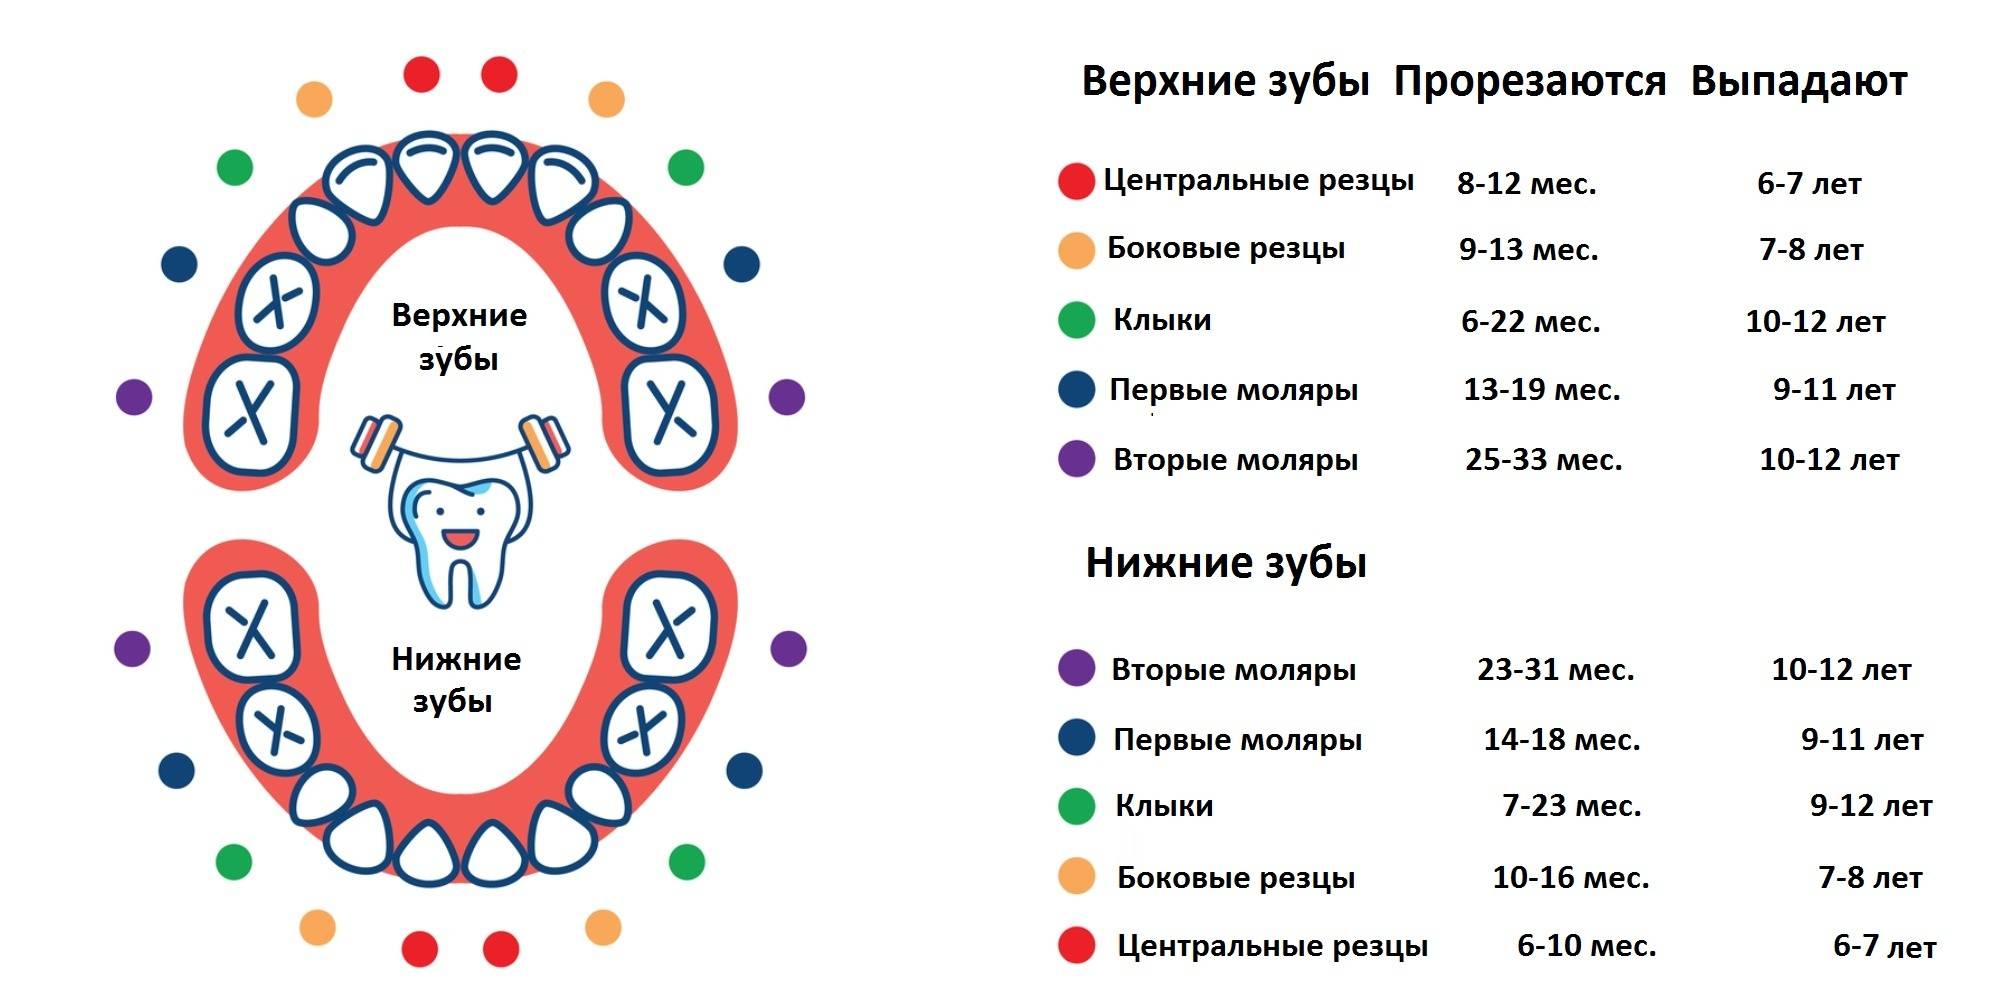

Приблизительная очередность выпадения и смены зубов:

Возраст ребенка Зубы

6 – 7 лет – Нижние, а за потом верхние центральные резцы, первые моляры

7 – 8 лет – Боковые резцы

9 – 10 лет – Первые премоляры

10 -11 лет – Прорезывание клыков, вторых премоляров

11 -13 лет – Вторые моляры

Когда выпадают молочные зубы у детей —схема

Когда выпадают молочные зубы у детей —схема

Молочные зубы у детей: схема выпадения

Выпадение начинается с резцов и далее в том же порядке, что и их прорезывание. В норме выпадать зубки у ребенка должны согласно следующему графику:

- Центральные резцы выпадают к 6-7 годам.

- Вторые резцы начинают выпадать к 7-8 годам.

- Первые моляры выпадают к 10 годам.

- Клыки и вторые моляры к 12 годам также заменяются на постоянные.

Стоит помнить, что возраст указан условно. Если сказано, что начинается выпадение в 6 лет, то смена может происходить в пять лет или в семь. Кроме того, коренные зубы у ребенка растут на свободном месте, поэтому появляются раньше, чем начинают выпадать молочные. Впервые прорезываются они иногда уже к пяти годам, но при этом они являются постоянными.